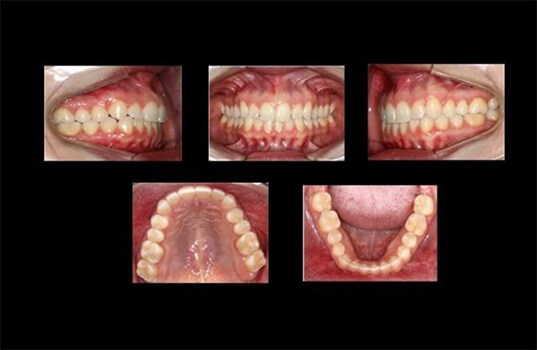

A documentação ortodôntica é um conjunto de exames usados para avaliar a posição dos dentes e das estruturas da boca, incluindo os maxilares, a mandíbula e as articulações Temporo-mandibulares. É uma ferramenta valiosa na avaliação e tratamento de problemas ortodônticos, como mordida aberta, apinhamento dentário, dentes torcidos ou desalinhados, e outros problemas estéticos ou funcionais da boca.

A documentação ortodôntica inclui radiografias, moldes de gesso da boca, fotografias, registros de movimento da mandíbula, entre outros. O dentista usa estas informações para avaliar a posição dos dentes, as relações dentárias e o funcionamento da boca como um todo. Com base nesta avaliação, o dentista pode decidir qual é o melhor tratamento ortodôntico para o paciente, se necessário.